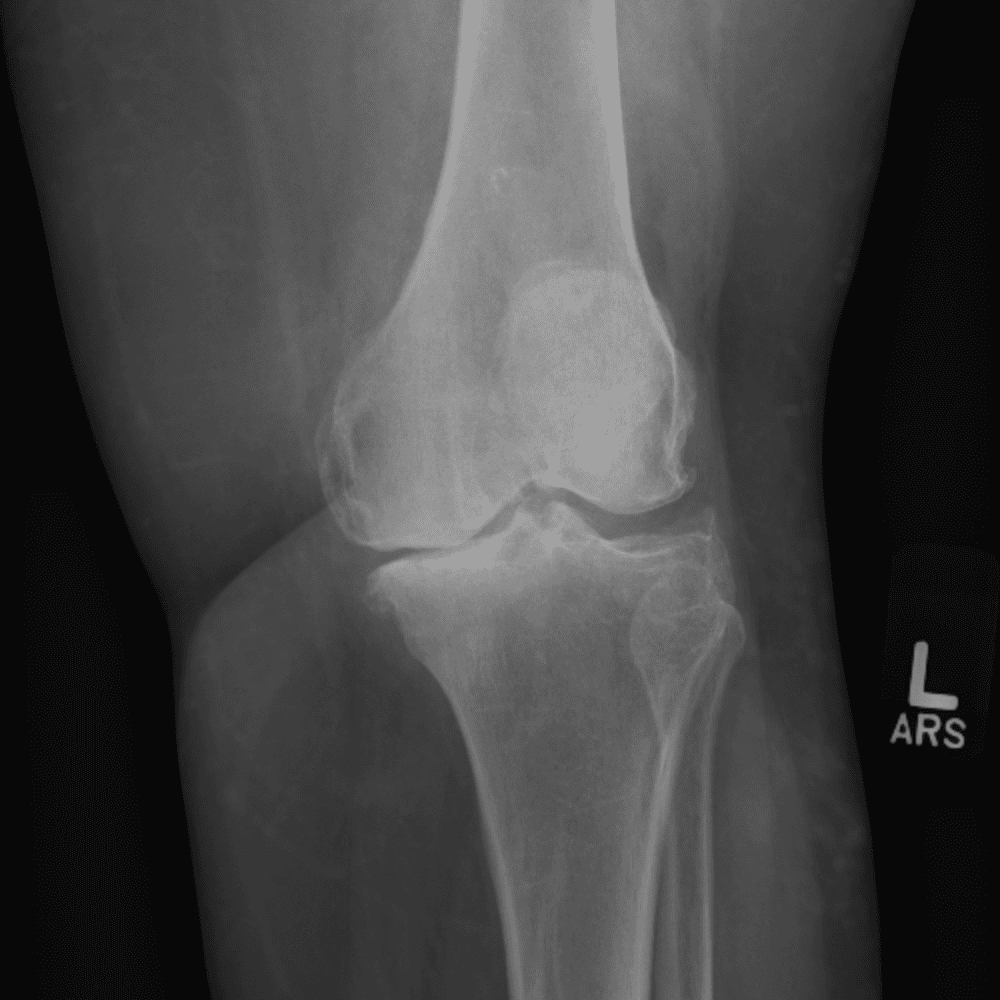

Simula o plantão incluindo casos sutis ou difíceis e alguns normais.